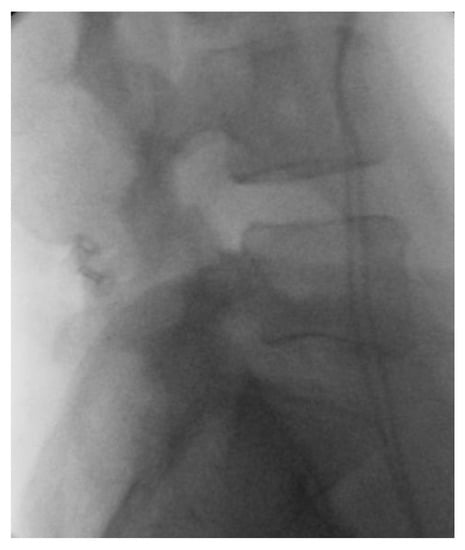

- Mohar, J. Sacroiliac Fixation with the Aid of a Personalized Navigational Guide in a Patient with Currarino Syndrome. J. Case Rep. Imaging 2020, 4, 100013. [Google Scholar]

- Farshad, M.; Selman, F.; Burkhard, M.D.; Müller, D.; Spirig, J.M. Partial Sacrectomy with Patient-Specific Osteotomy Guides. N. Am. Spine Soc. J. NASSJ 2021, 8, 100090. [Google Scholar] [CrossRef]